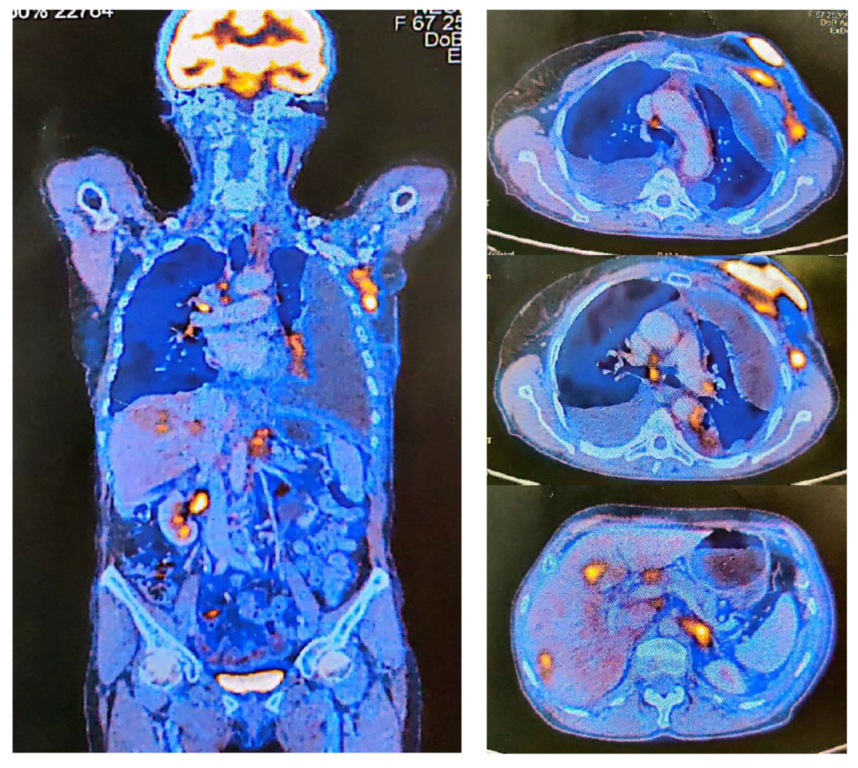

2. Case Report

| PET-CT | Positron Emission Tomography |

| SUV | Standardized Uptake Values |